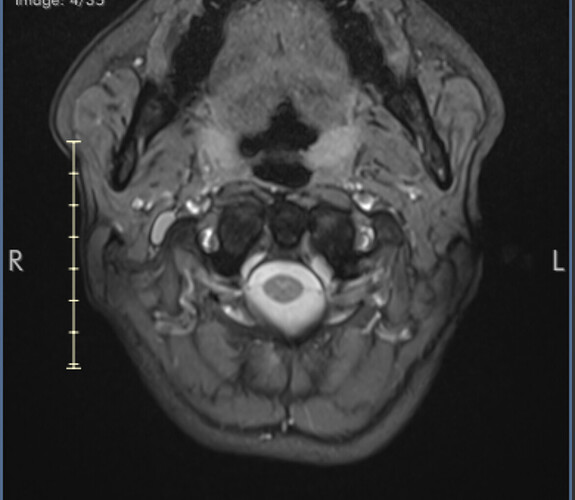

First stage of diagnosis - MRI images

I’ve uploaded some images now. I know they aren’t ideal but I’ll hopefully get my hands on the CT angiogram I had at A&E soon.

I marked the images for you and marked the IJV.

So you can see how the IJV passes by the transverse processes of C1 which are compressing. In this position the right IJV does not have severe compression, but in Figure 2 you can see that the left IJV is almost invisible, and in the other images there is significant narrowing.

On MRI, it is very difficult to see the styloid processes.